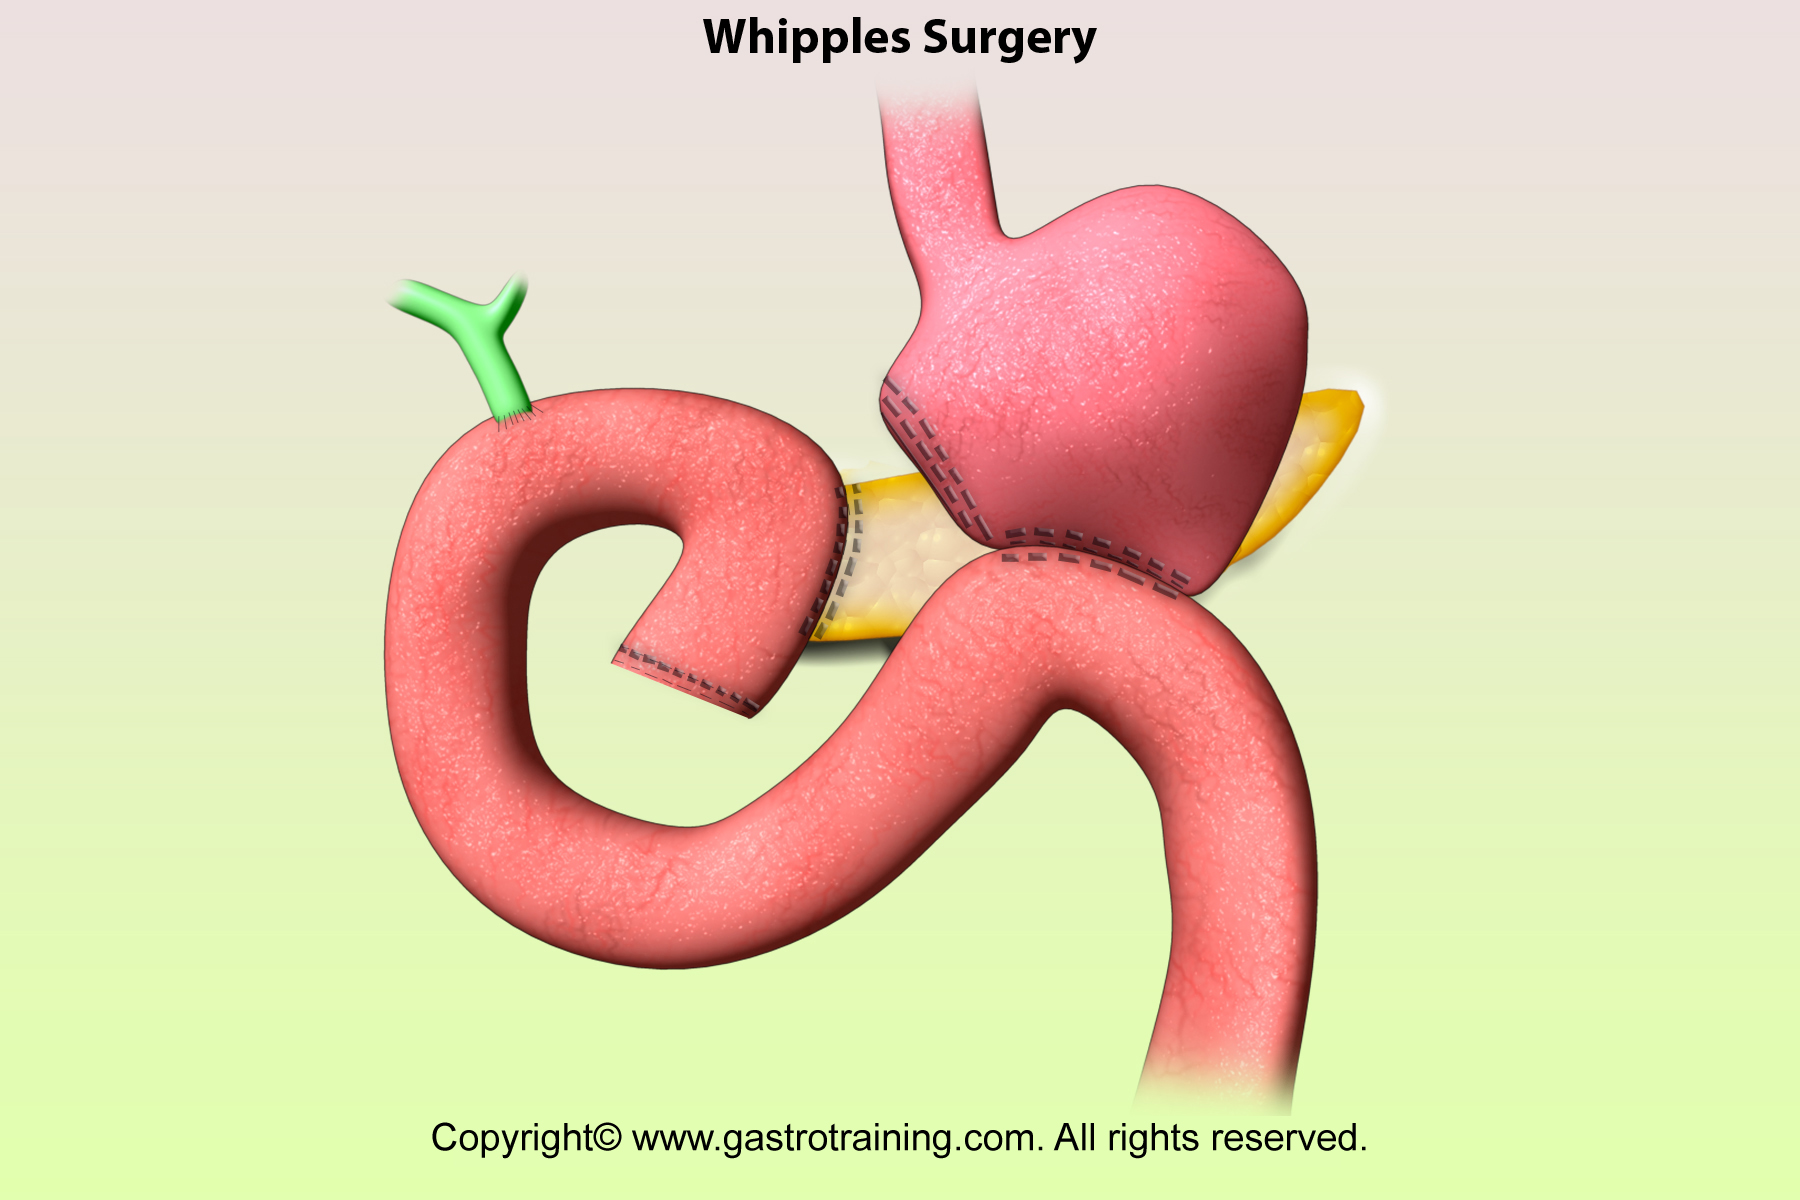

Фотографии медицинских исследований инсулиномы и синдрома Триады Уиппла